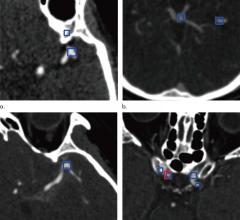

March 31, 2021 — Face masks may contain metallic components, both visible and hidden, which in the magnetic resonance ...